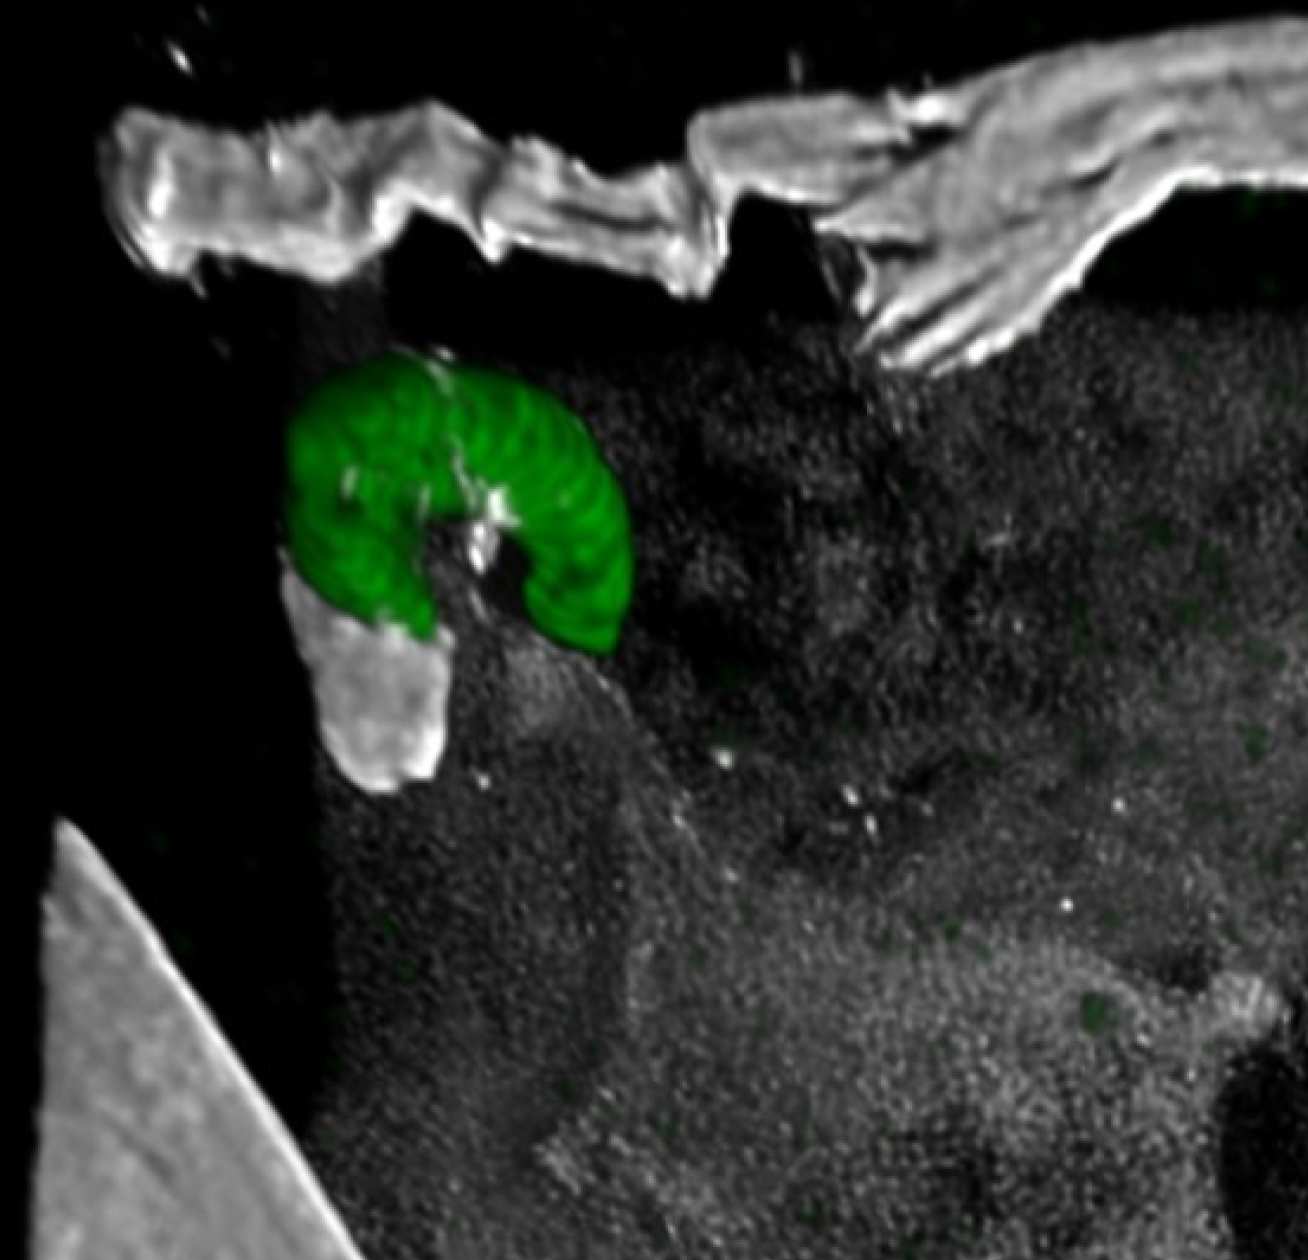

Red blob on the fringes of a cell with a green centre

A malaria parasite (red) entering a mosquito gut cell

The malaria parasite uses a specific molecule on its surface to get around a mosquito’s immune system, allowing it to invade and infect humans.

The group of parasites that cause malaria have a complex life cycle, having to pass through one of several certain species of mosquito before they can infect humans. The parasite enters a mosquito’s gut when it bites an infected human.